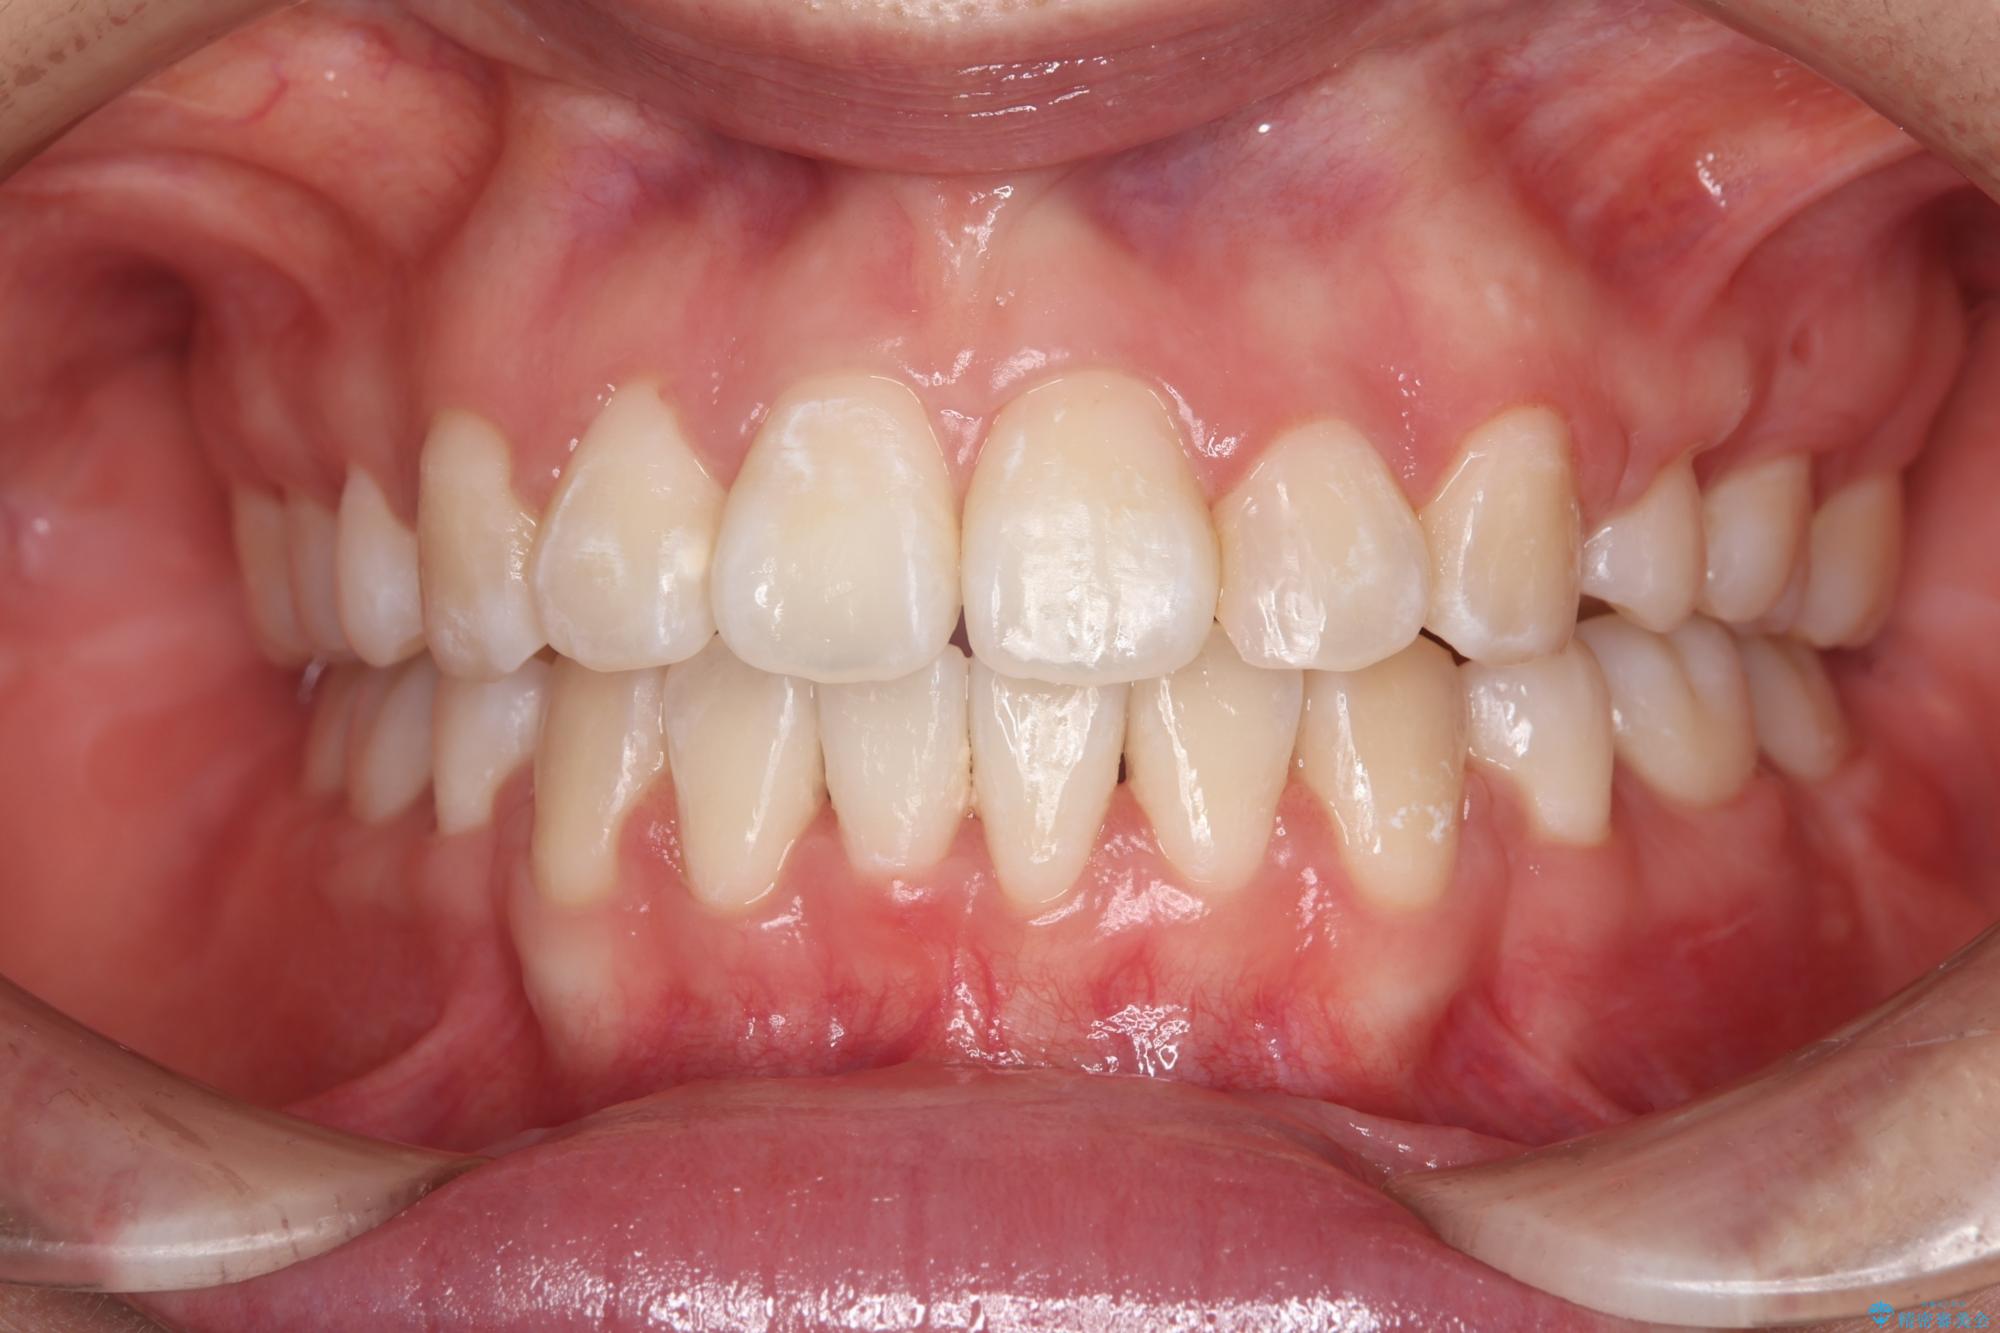

前歯のガつきと口元が出ていることを気にされご来院された患者様です。

上下4番目の歯を抜歯してガタつきを改善しながら口元を下げる治療計画を立てました。

抜歯矯正で口元を下げたことで、Eラインが大変綺麗になりました。